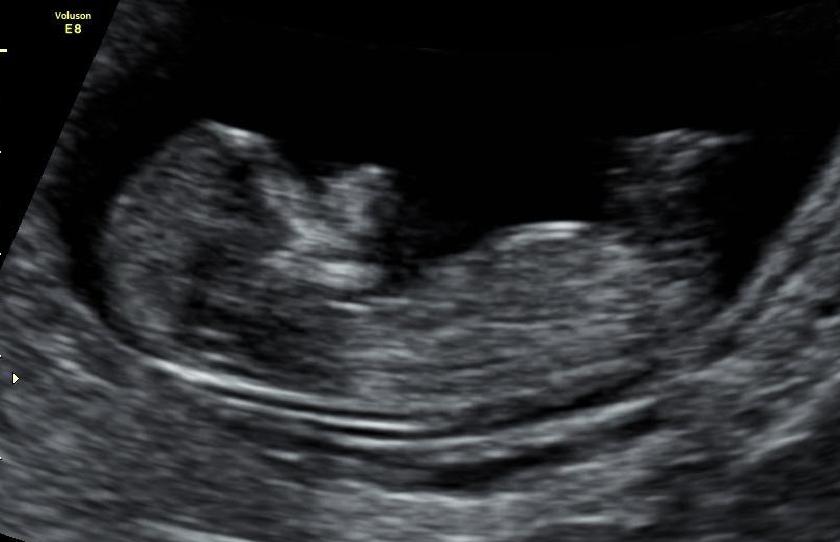

Hello All :) Last time I post this promise im just so excited to find out the gender.. Are there any Guesses on my babys 12 week ultrasound?? Il be sure to post the update on gender in here once I find out :) :)

Attachment 17439Attachment 17440Attachment 17441